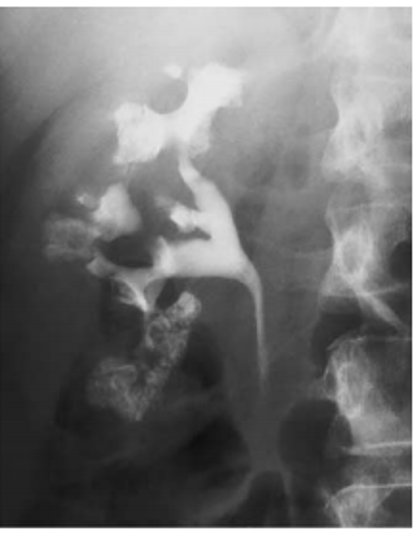

papillary necrosis